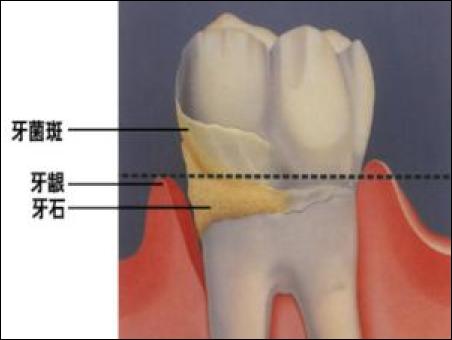

牙齒附著在牙槽骨上,外面包裹著牙齦。當牙周袋形成后,牙菌斑就會寄居于此,在牙菌斑細菌的作用下就會不斷地發(fā)炎,一方面它會侵蝕牙槽骨,讓牙槽骨慢慢地吸收;另一方面,牙齦腫脹發(fā)炎會降低牙齦與牙齒的附著力,兩種合力共同作用的結果,就是牙齒會越來越松動,直到失去固有的功能。

2、好好的牙齒為什么會形成牙周袋?

第二,是刷牙不好,尤其是下面的門牙,導致牙結石的滋生。